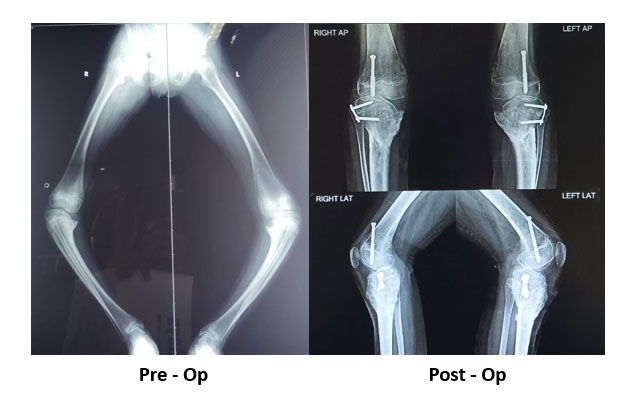

Blounts